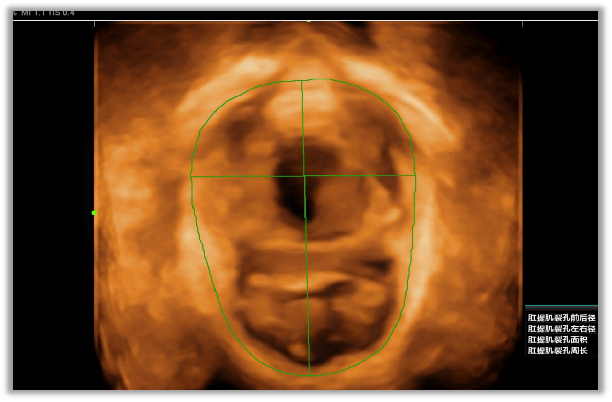

盆底超聲是利用超聲探頭經(jīng)會(huì)陰、陰道或直腸檢查,觀察在靜息、縮肛及Valsalva三種狀態(tài)下的盆腔臟器位置變化,結(jié)合多種成像方法(二維超聲、三維/四維容積超聲、斷層超聲成像)評(píng)估盆腔臟器脫垂程度、肛提肌裂孔大小及肛提肌、肛門內(nèi)外括約肌的完整性,同時(shí)能評(píng)估尿道、陰道及肛門周圍病變,也能用于盆底修復(fù)術(shù)前、術(shù)后及盆底康復(fù)療效的評(píng)估。具有無(wú)輻射、無(wú)創(chuàng)傷、可重復(fù)性好、實(shí)時(shí)動(dòng)態(tài)、價(jià)格低廉等優(yōu)勢(shì),有利于疾病的早期發(fā)現(xiàn)、早期診斷,在臨床癥狀出現(xiàn)前或癥狀較輕時(shí)通過(guò)物理治療來(lái)恢復(fù)盆底支持結(jié)構(gòu)功能,避免或者延緩手術(shù),提高患者生活質(zhì)量。

13.分娩后肛提肌評(píng)估